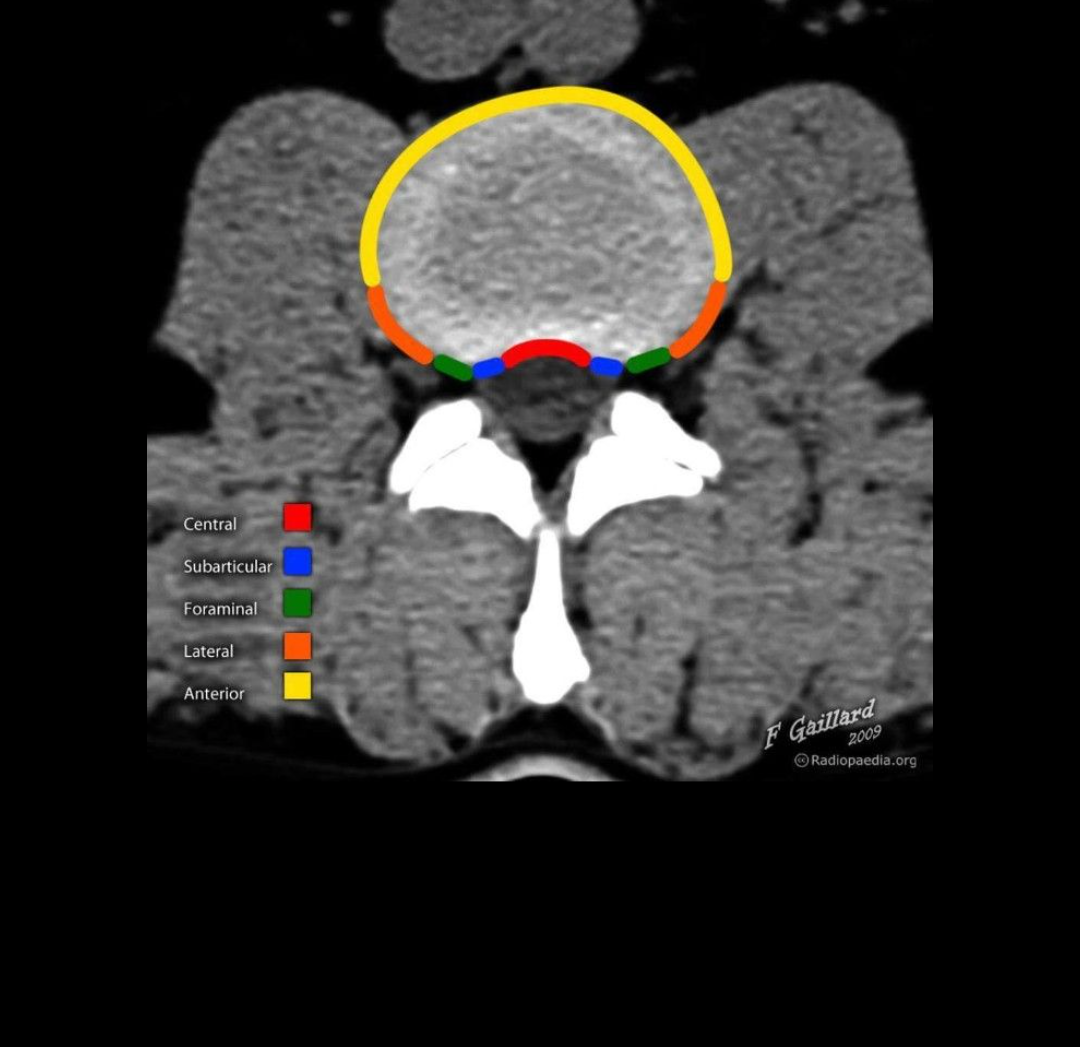

Тук можеш да видиш разликата между фораминална и екстрафораминална:

Също ѝ викат латерална на екстрафораминалната.